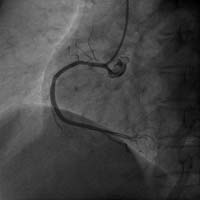

右冠狀動脈閉塞 介入術(shù)后右冠開通